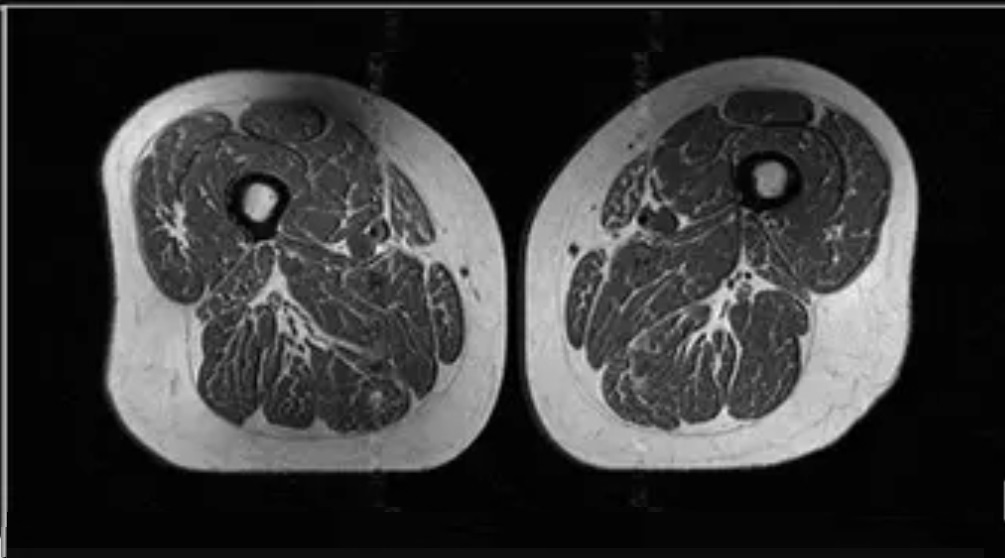

Η ένθετη φωτογραφία που παρατίθεται στη συνέχεια του κειμένου θυμίζει έντονα μπριζόλα πλούσια σε λεπτές λωρίδες λίπους. Στην πραγματικότητα όμως είναι η μαγνητική τομογραφία του μηρού μιας 62χρονης γυναίκας η οποία λατρεύει τα υπερεπεξεργασμένα τρόφιμα.

Η γυναίκα αυτή προσλαμβάνει το 87% των ημερήσιων θερμίδων της από πρόχειρα φαγητά, όπως κρύα δημητριακά πρωινού, μπάρες σοκολάτας, αναψυκτικά και εμφιαλωμένα ροφήματα με ζάχαρη.

Η ύπαρξη τόσο πολύ λίπους ανάμεσα στις μυϊκές ίνες του μηρού δεν είναι καλή ένδειξη, λένε οι ειδικοί. Και αυτό διότι αυξάνει τον κίνδυνο οστεοαρθρίτιδας στο γόνατο.

Οι ερευνητές κατέγραψαν τον δείκτη μάζας σώματος (ΔΜΣ) όλων των εθελοντών τους. Ανέλυσαν επίσης τη διατροφή τους και τους υπέβαλλαν σε μαγνητική τομογραφία μηρών. Το συνολικώς 65% των συμμετεχόντων ήσαν υπέρβαροι. Το περίπου 24% ήσαν παχύσαρκοι.

Ωστόσο οι μαγνητικές τομογραφίες έδειξαν πως το ενδομυϊκό λίπος στους μηρούς δεν επηρεαζόταν από το σωματικό βάρος τους. Ούτε έπαιζαν ρόλο οι θερμίδες που κατανάλωναν καθημερινή ή η άσκηση που έκαναν. Αυτό που ήταν καθοριστικό ήταν τα υπερεπεξεργασμένα τρόφιμα που έτρωγαν.

Στην πραγματικότητα, όσοι έτρωγαν συστηματικά τις μεγαλύτερες ποσότητες από αυτά, είχαν περισσότερο λίπος στους μυς των μηρών τους.